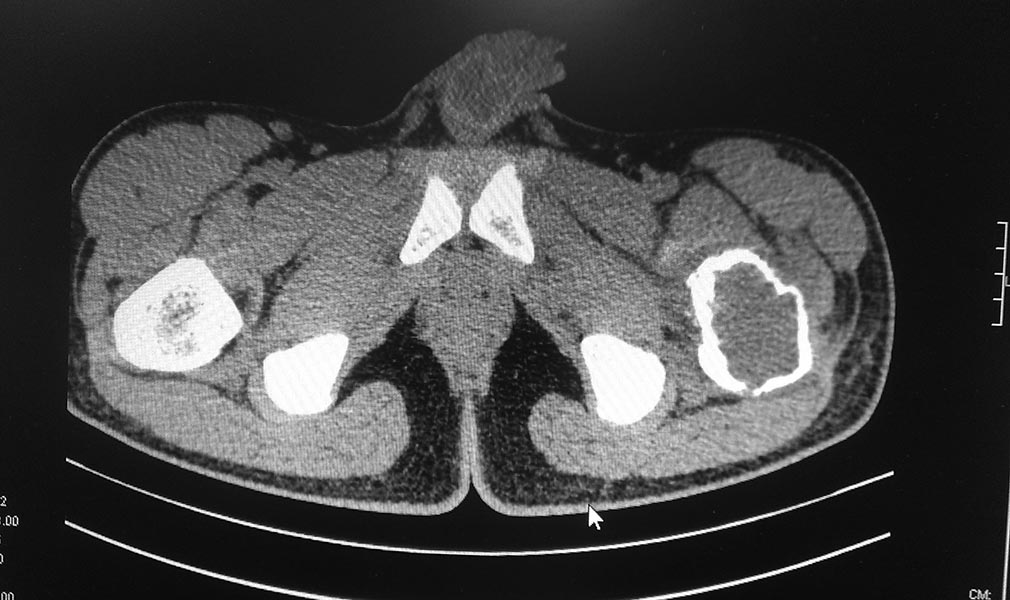

Уважаемые коллеги. Помогите определиться с тактикой лечения. Пациент 1993г.р (20 лет), поступил жалобами :на боли в области левого тазобедренного сустава, нарушение опорной функции левой нижней конечности.Anamnesis morbi: Со слов пациента и медицинской документации 15.08.2013г упал на область левого тазобедренного сустава. По скорой помощи госпитализирован в одну из клиник Астаны, где произведена рентгенография левого тазобедренного сустава, на которой выявлено образование проксимального отдела левой бедренной кости. Для выбора тактики дальнейшего лечение пациента, консультирован остеоонкологом, рекомендовано оперативное лечение в плановом порядке в условиях профильного отделения остеоонкологии АО «РНЦ НМП».Об-но: по внутренним органам без особенностей.Status localis: При осмотре пациент на кровати лежа на спине. Левая нижняя конечность без иммобилизации, ротирована наружу, в области левого тазобедренного сустава отмечается незначительный отек. Осевая нагрузка на левую нижнюю конечность болезненна. При пальпации отмечается резкая боль в области левого тазобедренного сустава. Симптом «прилипшей пятки» отрицательный с обеих сторон. Относительная длина обеих нижних конечностей одинаковая. На периферии конечностей нейроциркуляторных нарушений нет. На представленной R-грамме левого тазобедренного сустава–выявляется деструктивная полость в вертельной области левой бедренной кости нарушение костной структуры с образованием костной полости с тонкостенными перегородками.Границы полости крупно ячеистые. Госпитализирован с предварительным диагнозом: Остеобластокластома вертельной области левой бедренной кости. Закрытый патологический чрезвертельный перелом левой бедренной кости? 04.09.13г 1-м этапом произведена: Операционная биопсия из проксимального отдела левой бедренной кости. Заключение патолого - гистологического исследования: Патоморфологическая картина может соответствовать костной кисте. Пациенту произведено КТ обеих тазобедренных суставов. Заключение: КТ - признаки объемного образования области шейки и большого вертела левой бедренной кости дифференцировать с фиброзной дисплазией. Сростающийся патологический чрезвертельный перелом левой бедренной кости. ОАК, ОАМ, коагулограмма в пределах нормы.